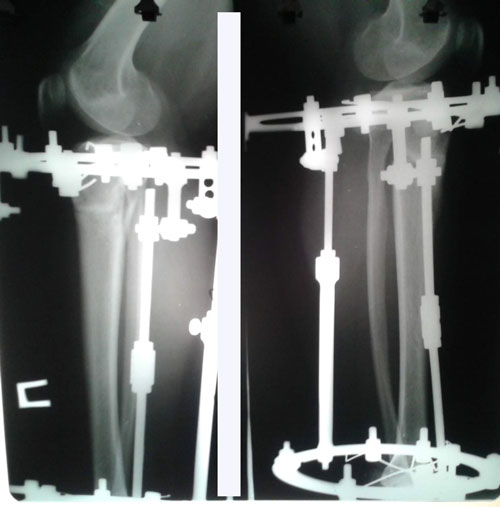

Диагноз: ахондроплазия, варусная деформация обеих голеней 155 градусов.

Дата операции 08.07.2015г.

Исходник.